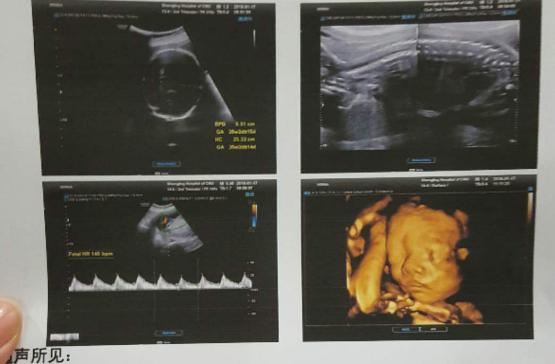

怀孕11-13周:抽血和超声筛查(NT检查)

怀孕14-21周:孕中期抽血筛查(唐氏筛查),一般是怀孕16周检查,若结果高危,需做羊穿或无创进一步排除;

怀孕20-28周:排畸B超,也有助及早发现胎儿异常。